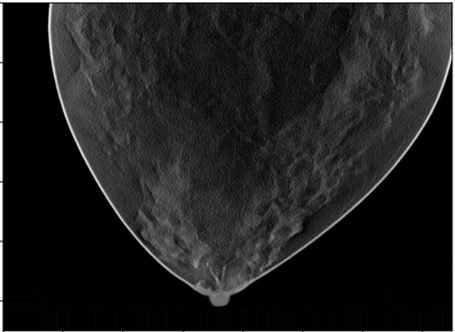

The DBT simulations were generated using the VICTRE pipeline [3]. We used the VICTRE software tools for phantom generation, X-ray production, and volume reconstruction. The X-ray projection was modeled using the Monte Carlo method based on tissue-radiation interaction physics. Simulated digital breast tomosynthesis (DBT) images were generated using an X-ray source operating at 30 kVp. The acquisition protocol included 25 projection images uniformly distributed over a 50-degree angular range. Image reconstruction was performed using a filtered back projection (FBP) algorithm, producing a voxel size of 0.1 . We generated breast images for three different breast densities, corresponding to the "mostly fatty", "scattered areas of dense" and "heterogeneously dense" categories described in the BI-RADS report. A spiculated mass (10 mm radius) was created at random locations near terminal duct lobular units. Examples are shown in Figs. 1(a)–1(c)

Results of applying both pipelines on a 2D DBT slice from a fatty density phantom are shown here, more results could be found in section 6. Fig. 2 shown the clustering result using GLCM mean and GLCM contrast from pipeline A. A mask is produced from the group that contained the lesion as Fig. 3. The final predicted candidates are shown in Fig. 4.